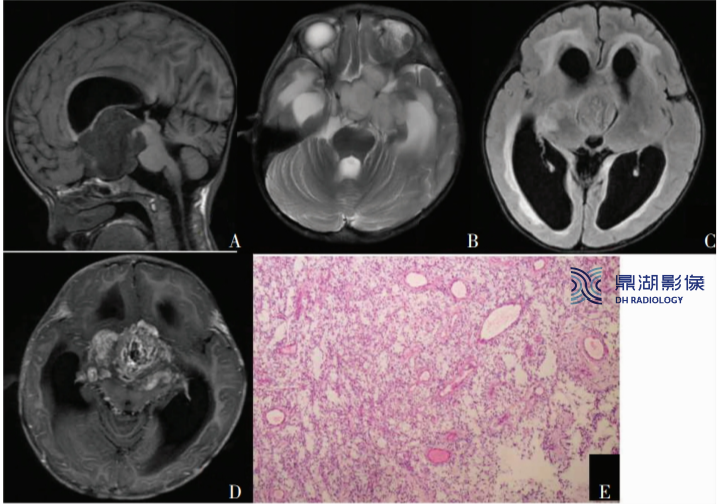

A.肿瘤在T1上呈低信号

B.肿瘤在T2上成均匀高信号,侵犯视交叉和视束

C.T2 FLAIR上成稍高信号,肿瘤侵犯丘脑和基底节区

D.增强后明显强化

E.肿瘤内血管明显增生,肿瘤细胞常围绕血管呈血管中心性排列